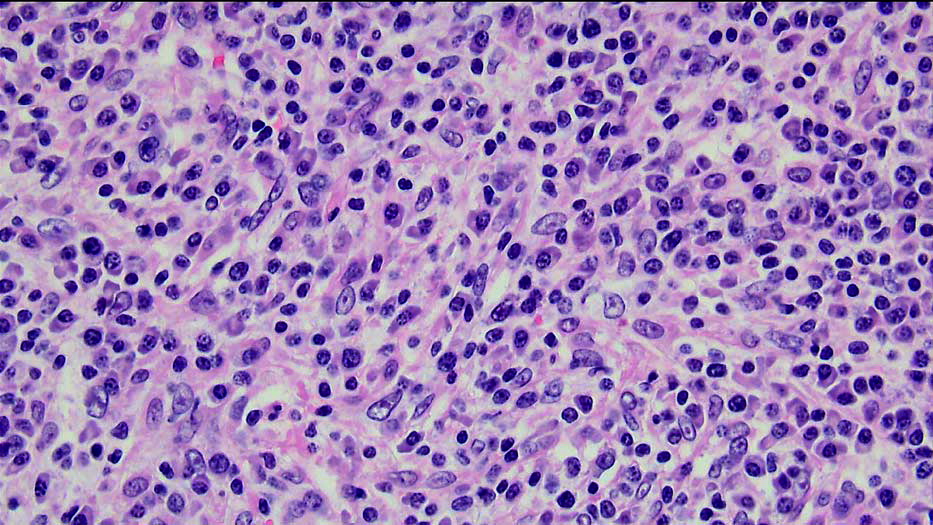

| 強拡大 |